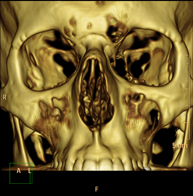

Prueba radiológica que consiste en obtener imágenes de la hipófisis cerebral de alta definición anatómica mediante el empleo de un equipo de TC (Tomografía Computarizada). Indicaciones: sospecha de tumor hipofisario, trastorno del crecimiento. - TC Macizo facial

Prueba radiológica que consiste en obtener imágenes del macizo facial (cara) de alta definición anatómica mediante el empleo de un equipo de TC (Tomografía Computarizada). Indicaciones: tumores, cirugía plástica. - TC Oídos